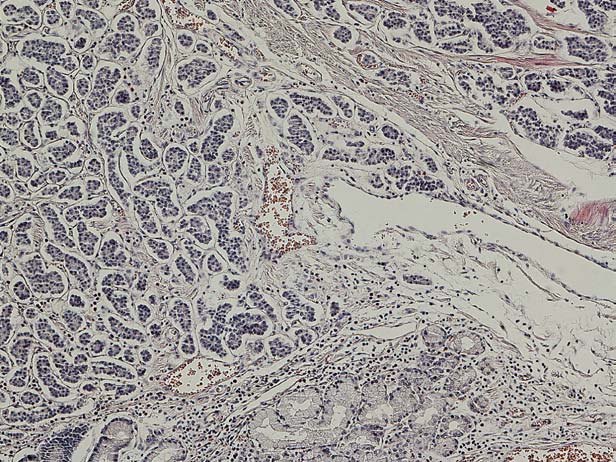

Obraz mikroskopowy guza neuroendokrynnego żołądka. Barwienie HE, powiększenie 10 ×